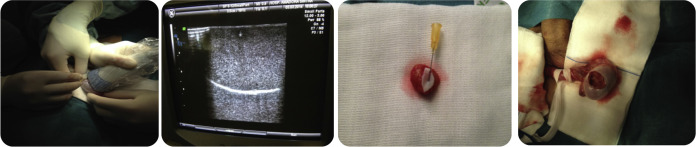

Apresentamos o caso clínico de um doente de 23 anos, saudável, que vem ao serviço de urgência do Hospital Prof. Doutor Fernando Fonseca por um quadro clínico de dor testicular à esquerda, com 3 dias de evolução, sem febre ou sintomas geniturinários. Ao exame objetivo apresentava palpação dolorosa ao nível da cabeça do epidídimo, sem evidência de varicocelo, hidrocelo ou hérnia inguino‐escrotal. Ambos os testículos eram normodimensionados, de consistência elástica e sem nódulos palpáveis. Na ecografia escrotal identificou‐se um nódulo periférico do parênquima testicular de 7,5 mm, hipoecogénico e sinal Doppler presente (fig. 1 ). Admitiu‐se orquiepididimite, para a qual fez antibioticoterapia empírica. Após resolução dos sintomas, realizou ecografia escrotal de controlo 15 dias e 30 dias depois, com persistência da mesma lesão e com as mesmas características. Os marcadores tumorais, alfafetoproteína, beta‐HCG e LDH revelaram‐se negativos; o perfil hormonal com níveis séricos de testosterona, LDH e FSH encontravam‐se dentro dos parâmetros normais e a TAC toracoabdominopélvica não demonstrou qualquer evidência de doença retroperitoneal ou à distância.

Nódulo hipoecogénico de 7,5mm com sinal Doppler presente.

Nódulo hipoecogénico de 7,5 mm com sinal Doppler presente.

Tendo em conta as características suspeitas da lesão, propôs‐se uma orquidectomia parcial, guiada por ecografia com exame extemporâneo. Por uma abordagem inguinal, o testículo foi libertado da bolsa escrotal e avaliado no campo operatório por ecografia (fig. 2 ). O nódulo foi marcado com uma agulha subcutânea, excisado e submetido a exame extemporâneo, em que se identificou macroscopicamente uma lesão sólida, amarela e elástica de 5 mm e cujo corte de congelação revelou uma proliferação neoplásica de padrão de crescimento nodular/sólido, constituída por células com anisocariose nuclear e citoplasma vasto e claro, por vezes eosinofílico – «neoplasia maligna do testículo, provável seminoma ». Perante o resultado, optou‐se pela totalização da orquidectomia e colocação de prótese testicular, com o resultado histológico final de «tumor das células de Leydig » ( fig. 3 ) e sem neoplasia intratubular germinativa (NITG). Com a exceção de ligeira anisocariose, não se observavam outros critérios morfológicos preditivos de malignidade, como um índice mitótico elevado (no caso presente caso, o índice era de uma mitose/10 campos de grande ampliação), necrose e/ou invasões vasculares. O tumor de células de Leydig (benigno) admite alguma atipia citológica, podendo dificultar a sua avaliação em cortes de congelação durante o exame extemporâneo. Aos 9 meses de seguimento, a ecografia escrotal de controlo não revelou qualquer nódulo de novo e os marcadores tumorais mantiveram‐se negativos. Pela ausência de critérios de malignidade, o seguimento consistirá numa consulta anual com exame objetivo, avaliação de marcadores tumorais e ecografia de controlo.

Orquidectomia parcial ecoguiada.